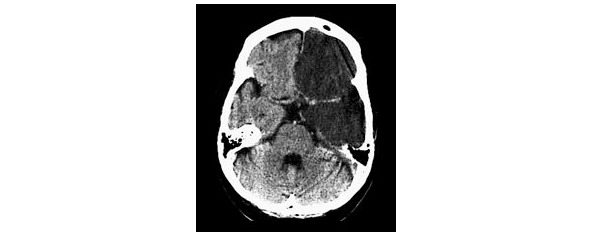

Ишемический инсульт обусловлен нарушением проходимости мозговых сосудов вследствие закупорки их атеросклеротической бляшкой, эмболом, тромбом или в результате спазма сосудов мозга различной локализации (рис. 1).

Рисунок 1. КТ-картина ОНМК по ишемическому типу в бассейне левой каротидной артерии